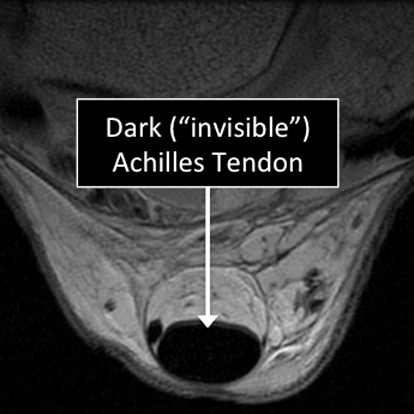

Ankle MRI examinations showing normal (top) and abnormal (bottom) Achilles tendon.

Why Translational MRI of the cartilage?

- Tendons are one of the several structures that can’t be seen (they look black or dark) with the standard MRI.

Ankle MRI examinations using the standard MRI techniques (top) and translational MRI techniques (bottom).